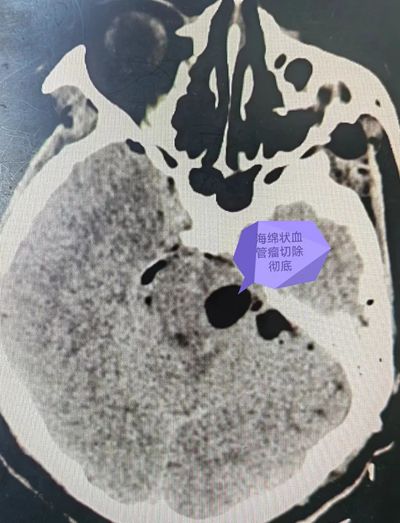

头颅CT提示左侧脑干出血,进一步做头颅MR(核磁共振)检查提示为左侧脑干海绵状血管瘤伴出血。

“海绵状血管瘤虽然叫瘤但却不是瘤,它其实是一个畸形血管团,外形上看很像一颗爆米花。”我院神经外科学科带头人、主任医师谢正兴介绍,海绵状血管瘤会使脑干不断受到压迫,在某些诱发因素如外伤、高血压、情绪激动等情况下,可能引发出血。

当下刘玫的脑干海绵状血管瘤已经发生了出血,入院后,她又出现了肢体麻木、乏力等症状,谢主任判断其脑干再次出血的可能性大,如果放任不管,致死致残的几率会大大增加。